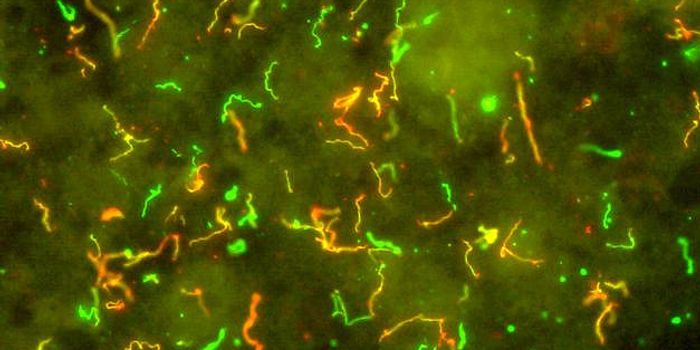

AUG 25, 2016MicrobiologyResearchers have learned more about how Lyme disease invades the body, and will publish their findings September 6 in Ce ...